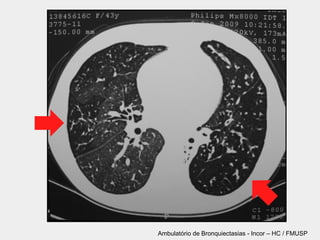

TC de tórax

§ Padrão ouro

§ Definição tomográfica

§ Anel de sinete

§ Não redução gradual do brônquio

§ Brônquio visualizável a 1 cm da pleura

TC de tórax §Padrão ouro § Definição tomográfica § Anel de sinete § Não redução gradual do brônquio § Brônquio visualizável a 1 cm da pleura